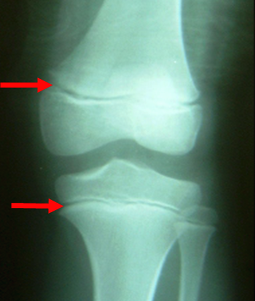

X-ray로 성장판을 검사하면 손이나 골반, 무릎관절, 팔꿈치관절, 발목관절을 사용해서 골연령을 평가하는데요.

성장판 검사는 나이에 따라 검사 부위가 다른데 청소년의 경우 어깨를 같이 찍기도 하고, 1세 미만의 경우 무릎 사진을 같이 찍기도 합니다.